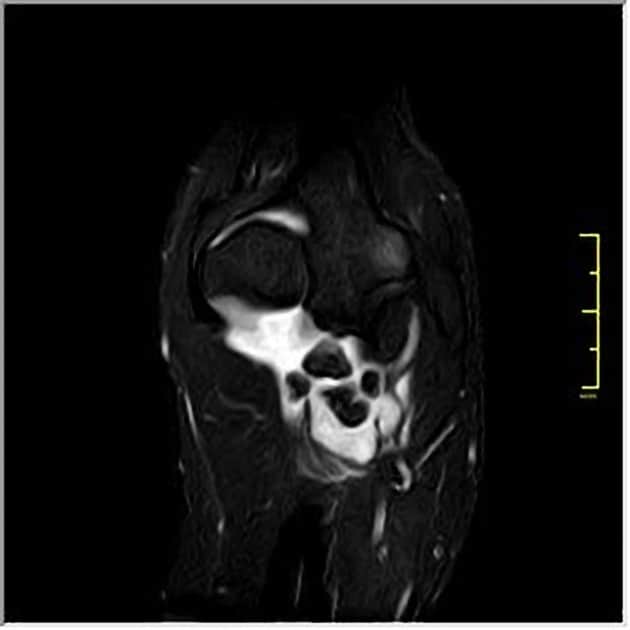

U sụn màng hoạt dịch

» Thông tin: Nữ giới – 32 tuổi.

» Lâm sàng: Đau khuỷu tay 2 năm.